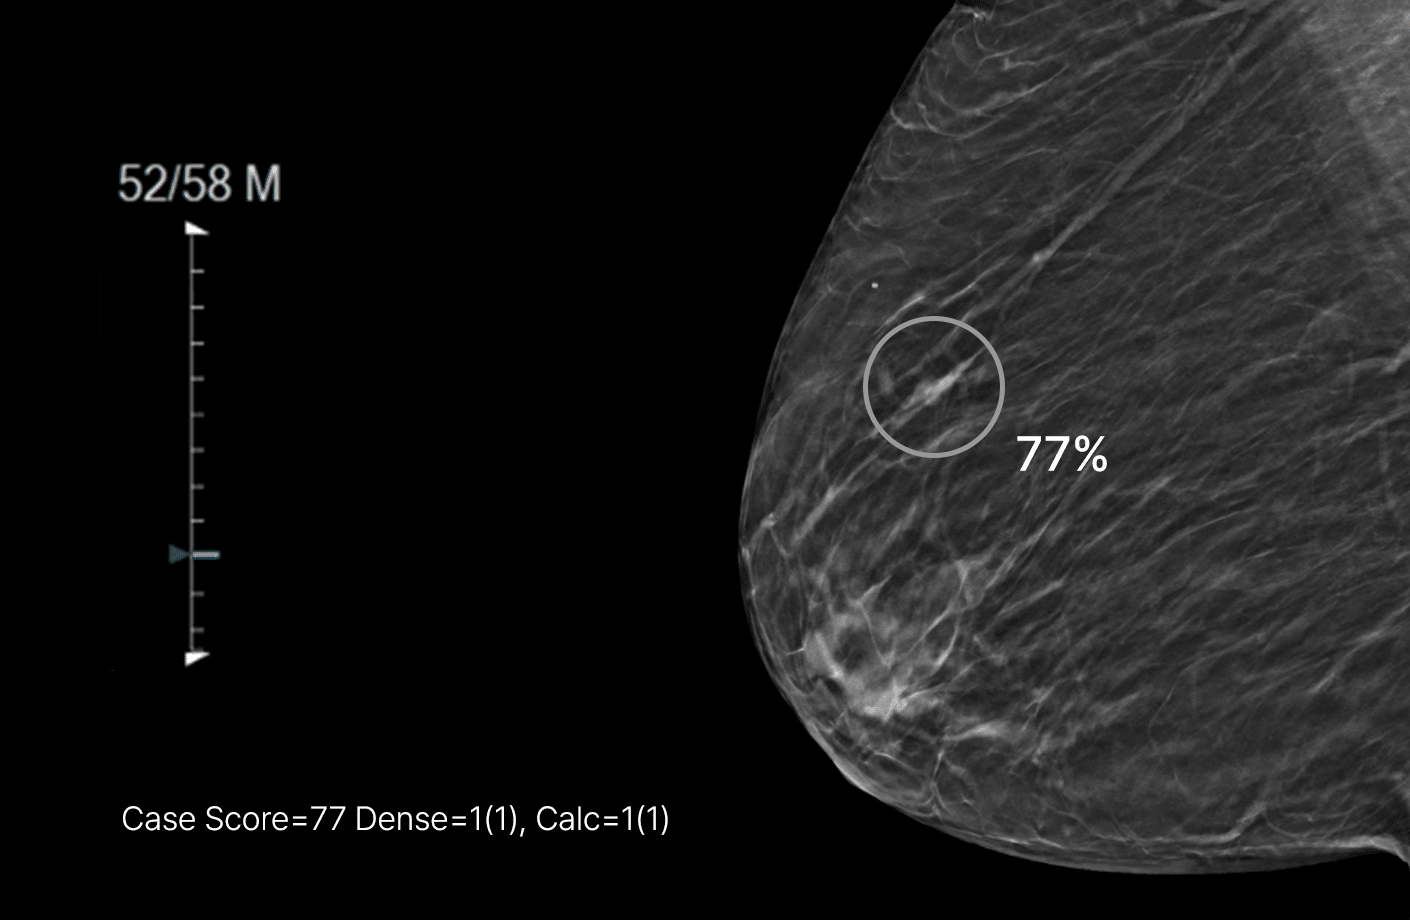

루닛 인사이트 DBT는 유방단층 촬영 영상을 분석해 유방암 의심부위의 위치와 유방 내 병변이 존재할 가능성을 0~100 범위의 점수로 표시합니다.

또한 병변 유형을 세 가지로 표시합니다.

분석결과는 별도 생성되는 영상 혹은 원본 영상 위에서 확인할 수 있습니다.